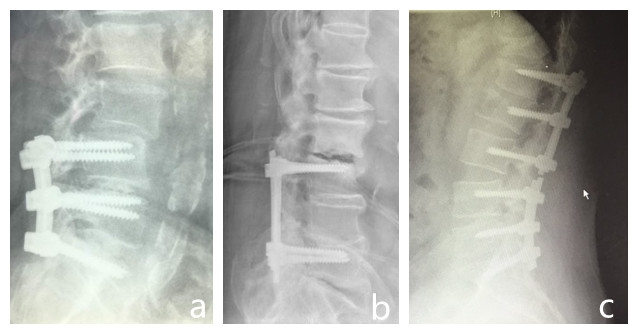

图1 脊柱融合固定相关并发症

a~f依次为:半脱位、ASD、UIV+1骨折、术后脱位、固定椎上方骨折、邻近节段问题半脱半